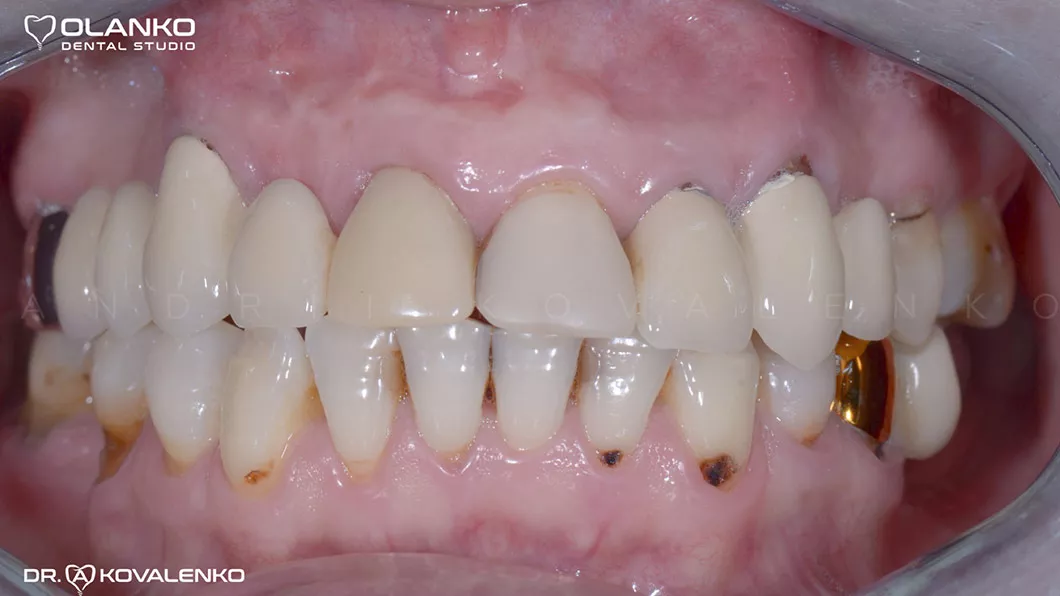

Ситуация до

Пациентка обратилась с жалобами на неудовлетворительный внешний вид старых коронок и мостовидных протезов, а так же дискомфорт и боль при жевании, в связи со значительной подвижностью конструкций.